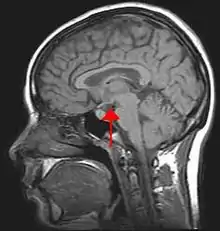

Hypothalamus et motivation

L'hypothalamus peut être également associé à la motivation de comportement assouvissant certains besoins physiologiques tels que la soif et la faim. Cet « expert » du système végétatif, est le « commandeur » de ces comportements. En effet, « l'hypothalamus peut être considéré comme un véritable ordinateur de la vie végétative qui programme les composantes physiologiques de la faim, de la soif, de la sexualité, de l'ovulation, les rythmes de base du sommeil, etc. »[30]. De plus, ce deuxième facteur explicatif de la motivation est directement relié au système limbique, qui est au centre des émotions humaines, et ainsi, permet de déclencher, ou inhiber, des comportements agressifs.

Par exemple, la stimulation de l'hypothalamus médian ventral entraîne le déclenchement de la lutte, alors qu'au niveau dorsal, il déclenche la fuite. L'hypothalamus latéral, stimulé cholinergiquement, déclenche soit la soif, soit l'agressivité.

Les images par la résonance magnétique (IRM) contemporaine ont procuré un support empirique solide pour la théorie psychologique selon laquelle la programmation émotionnelle est largement définie dans l’enfance, d’autant qu’à l’âge de neuf mois le cerveau a déjà 95 % du volume qu’il aura à l’âge adulte.